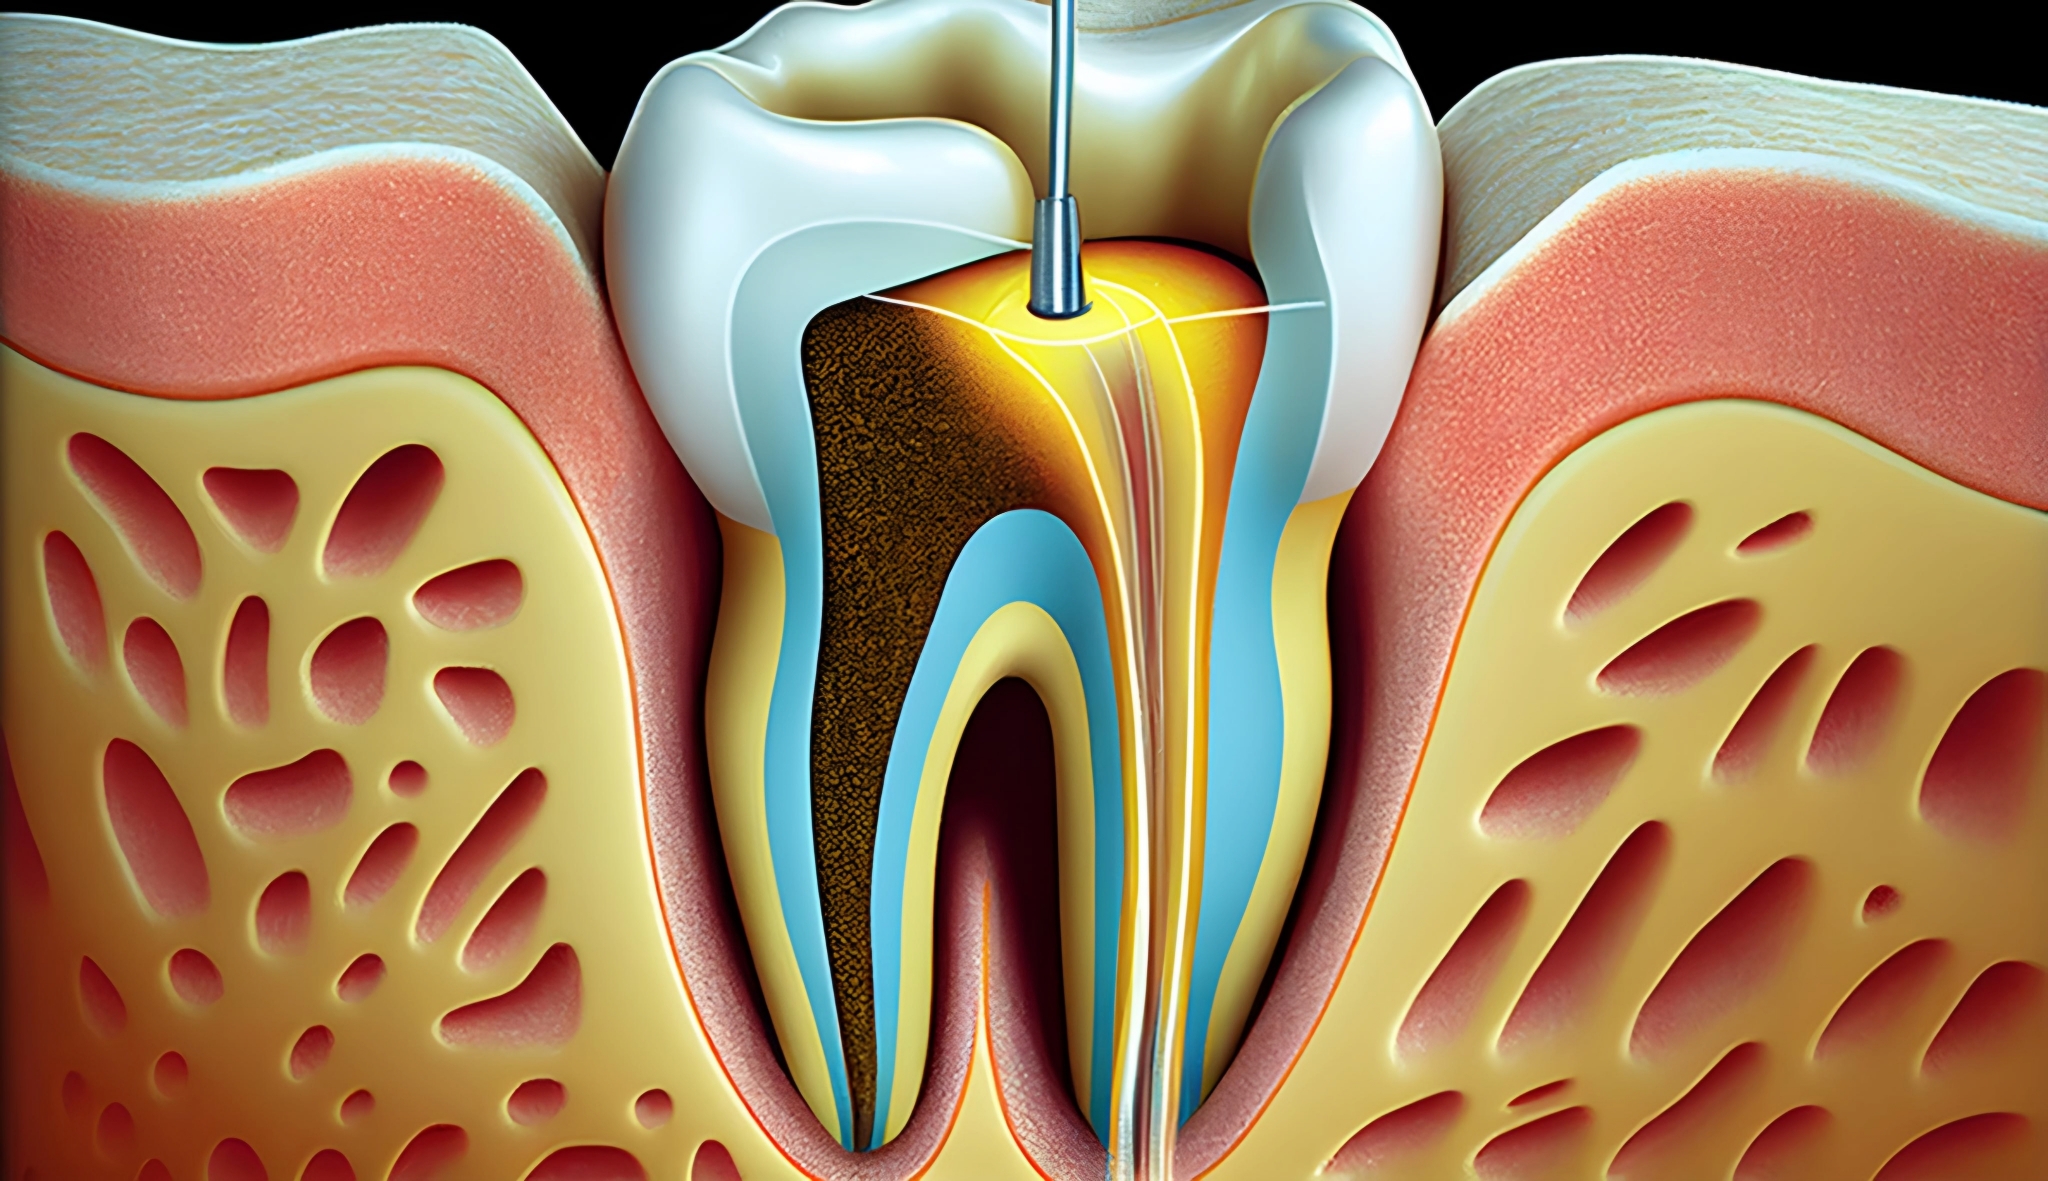

مغز دندان یا پالپ دندان (به زبان انگلیسی: Pulp) به رگها و اعصاب دندان می گویند. حفره مرکزی در تاج دندان، اتاق پالپ نامیده می شود. مجرای ریشه دندان را نیز کانال دندان نامیده می شود. در حالت عادی مغز دندان زنده و فعال است ولی پوسیدگیها و آزردگیهای رگها و عصبها باعث درد و سرانجام مرگ مغز دندان، و از بین رفتن مغز دندان می شود.

هنگامی که مغز دندان به هر علتی دچار آزردگی شدید شد درمان ریشه دندان ضرورت پیدا میکند.